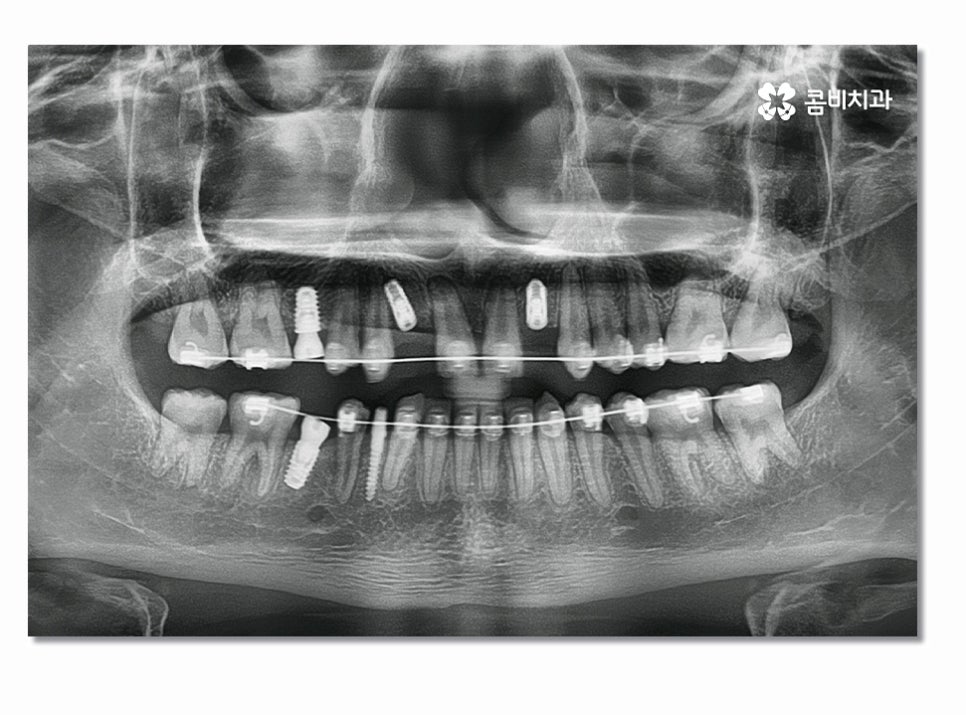

앞니임플란트의 경우 어금니에 비해 시술 난이도가

높은 편인데 심미적인 부분도 중요하며 임플란트의

식립 각도, 윗니와 아랫니의 교합에 대한 이해도,

잇몸 상태, 인접 치아와 자연스러운 결과 등

다각도로 판단해야 하기 때문에 의료진의 경험과

3D CT 등을 활용한 정확한 검진이 중요하다고 할 수 있어요.

특히 위 환자분의 경우에는 앞니 올 세라믹 치료와

치아교정, 임플란트를 동시에 진행해야 했기 때문에

전체적인 조화와 치료 계획을 철저하게 세울 필요가 있었고

앞니임플란트와 함께 주변 치아가 심미적으로

자연스럽게 어울리면서 교합까지 잘 체크해야 했기 때문에

유독 여러 측면에서 섬세한 치료가 필요했다고 볼 수 있어요.